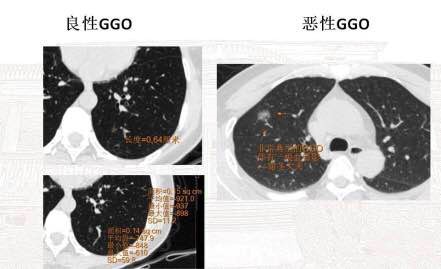

王主任分析了磨玻璃结节的良恶性几率

及其相关知识